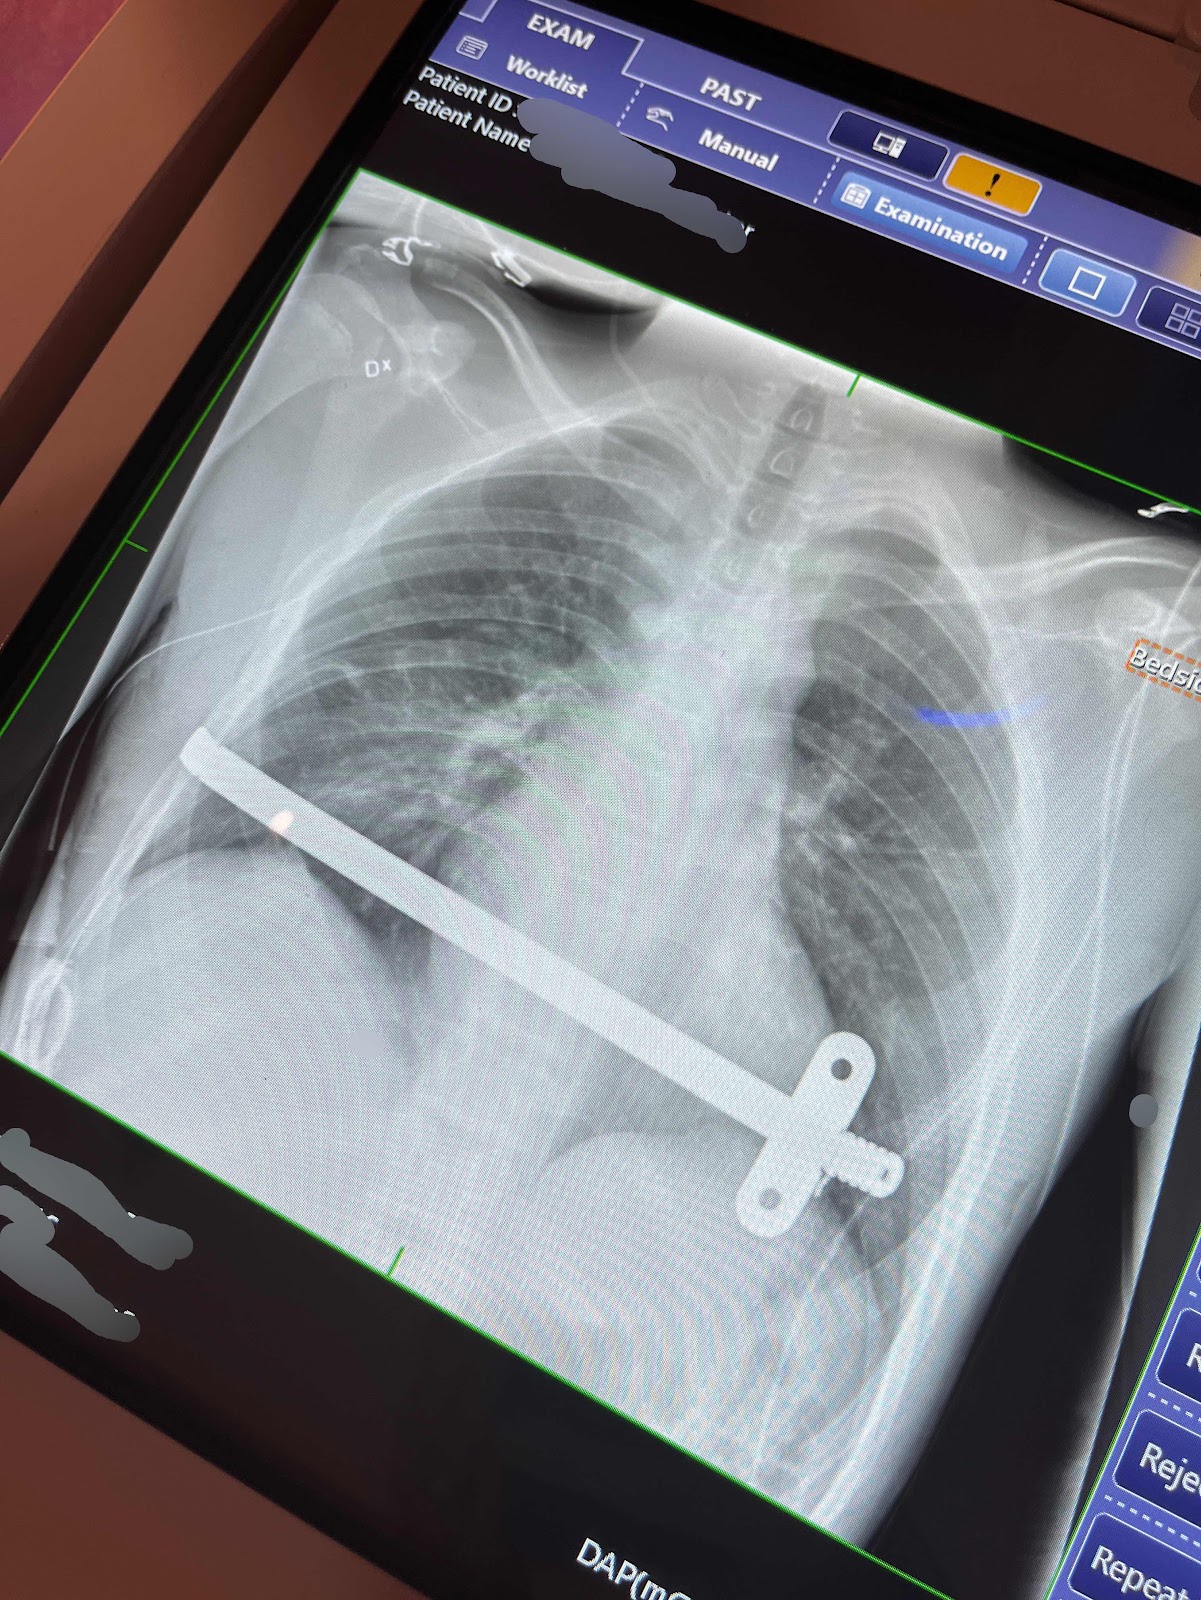

Strax före tre ringde kirurgen och berättade att det var klart och en stund senare kom Oskar till avdelningen och en särskild, övervakad sal där han skulle ligga de första sex timmarna. De gjorde en lungröntgen på honom.